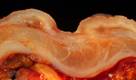

https://commons.wikimedia.org/wiki/File:Benign_gastric_ulcer_3.jpg

Description    Benign gastric ulcer

This photo presents the same case

shown in Image:Benign gastric ulcer 1.jpg and Image:Benign gastric ulcer 2 (wet).jpg.

The photo is a of a longitudinal

section of the ulcer and adjacent gastric wall. Note that the normal anatomic

layers are discrete and relatively undisturbed as compared with the homogenation of the wall and caused by some malignant

ulcers.

Photograph by Ed Uthman, MD. Public

domain. Posted 23 Sep 00

Modifed: A.G. DiGiovanna

Added labels and

lines.